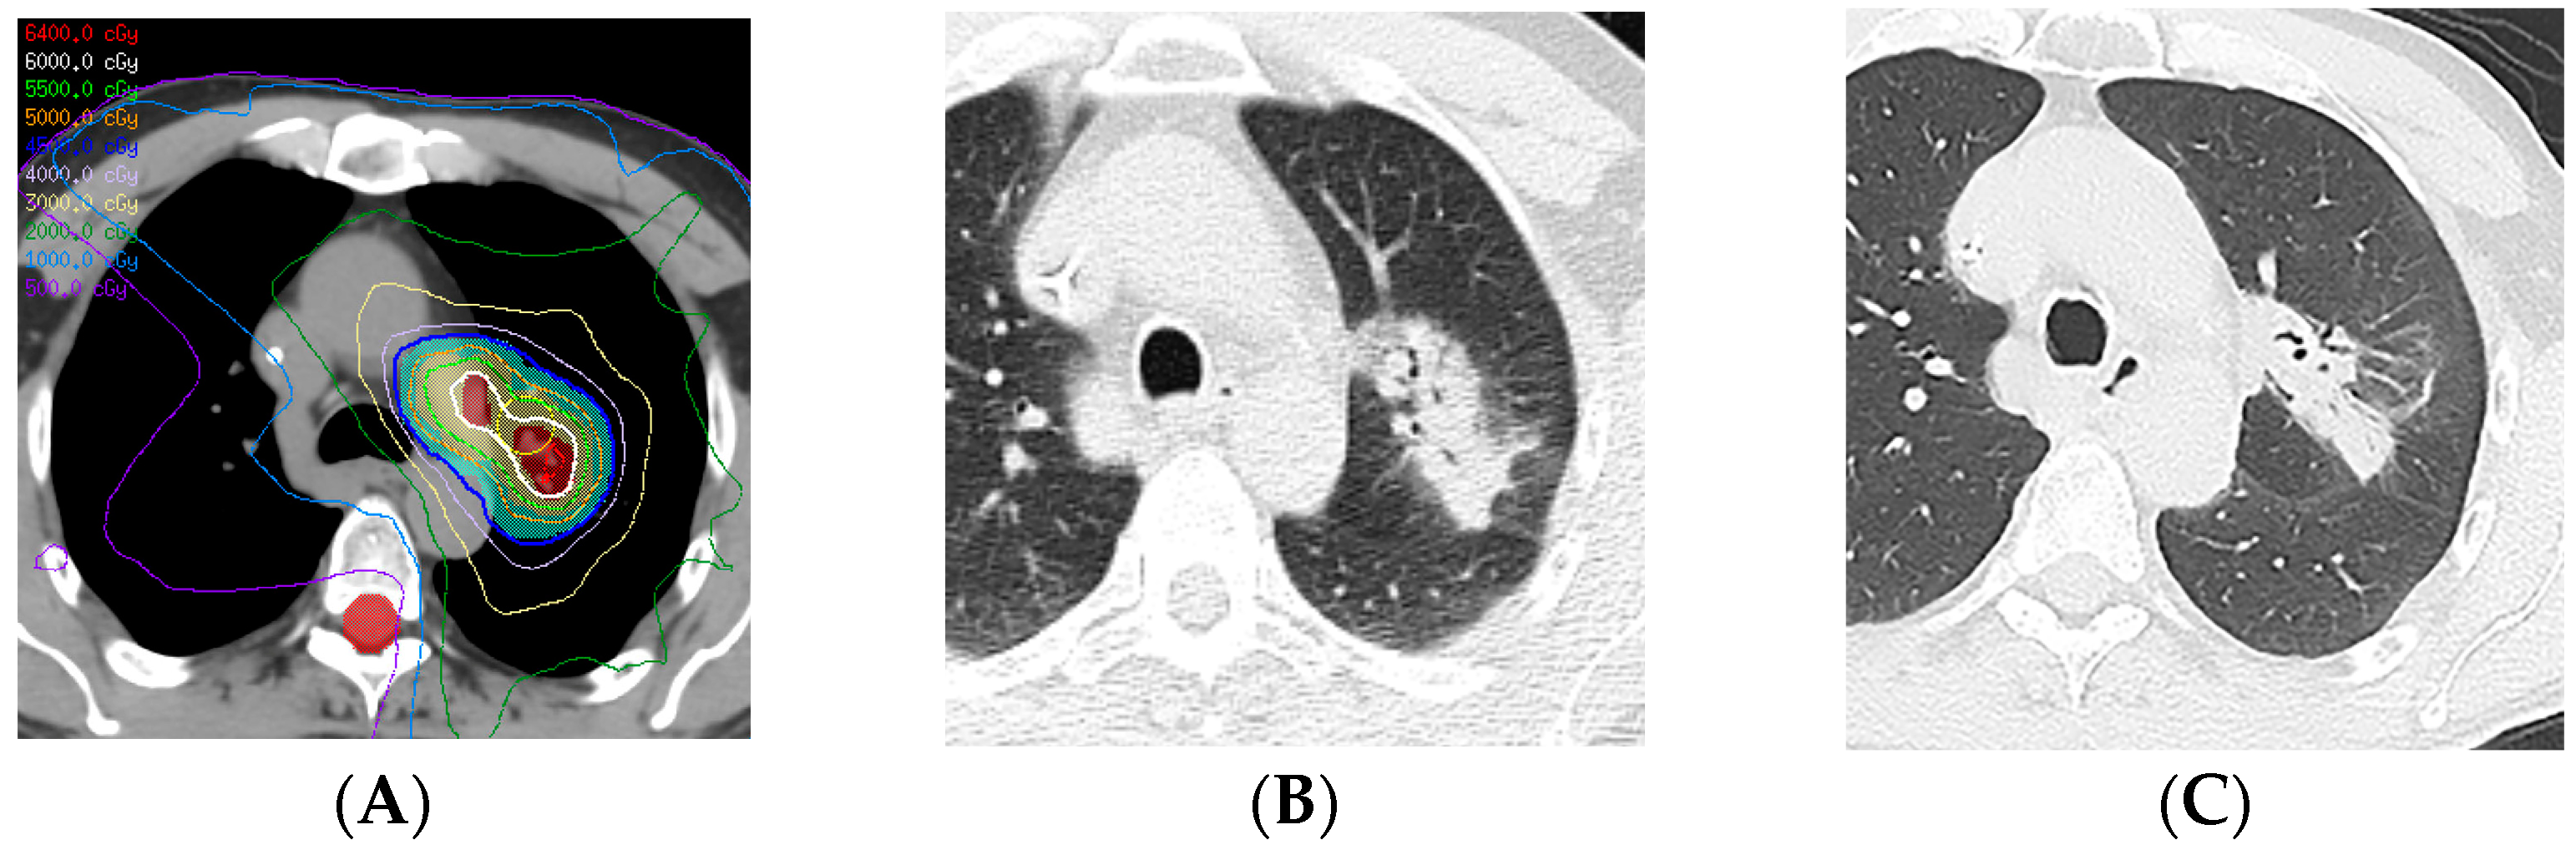

- Nakamura, N.; Hojo, H.; Inoue, K.; Hotta, K.; Zenda, S.; Baba, H.; Onozawa, M.; Motegi, A.; Nakamura, M.; Kibe, Y.; et al. Late radiological changes after passive scattering proton beam therapy for Stage I lung cancer. J. Radiat. Res. 2018, 59, 456–461. [Google Scholar] [CrossRef]

- Yang, Y.; Li, G.; Li, S.; Wang, Y.; Zhao, Y.; Dong, B.; Wang, J.; Zhu, R.; Chen, M. CT Appearance Pattern After Stereotactic Body Radiation Therapy Predicts Outcomes in Early-Stage Non-Small-Cell Lung Cancer. Front. Oncol. 2021, 11, 746785. [Google Scholar] [CrossRef]

- Kato, S.; Nambu, A.; Onishi, H.; Saito, A.; Kuriyama, K.; Komiyama, T.; Marino, K.; Araki, T. Computed tomography appearances of local recurrence after stereotactic body radiation therapy for stage I non-small-cell lung carcinoma. Jpn. J. Radiol. 2010, 28, 259–265. [Google Scholar] [CrossRef]